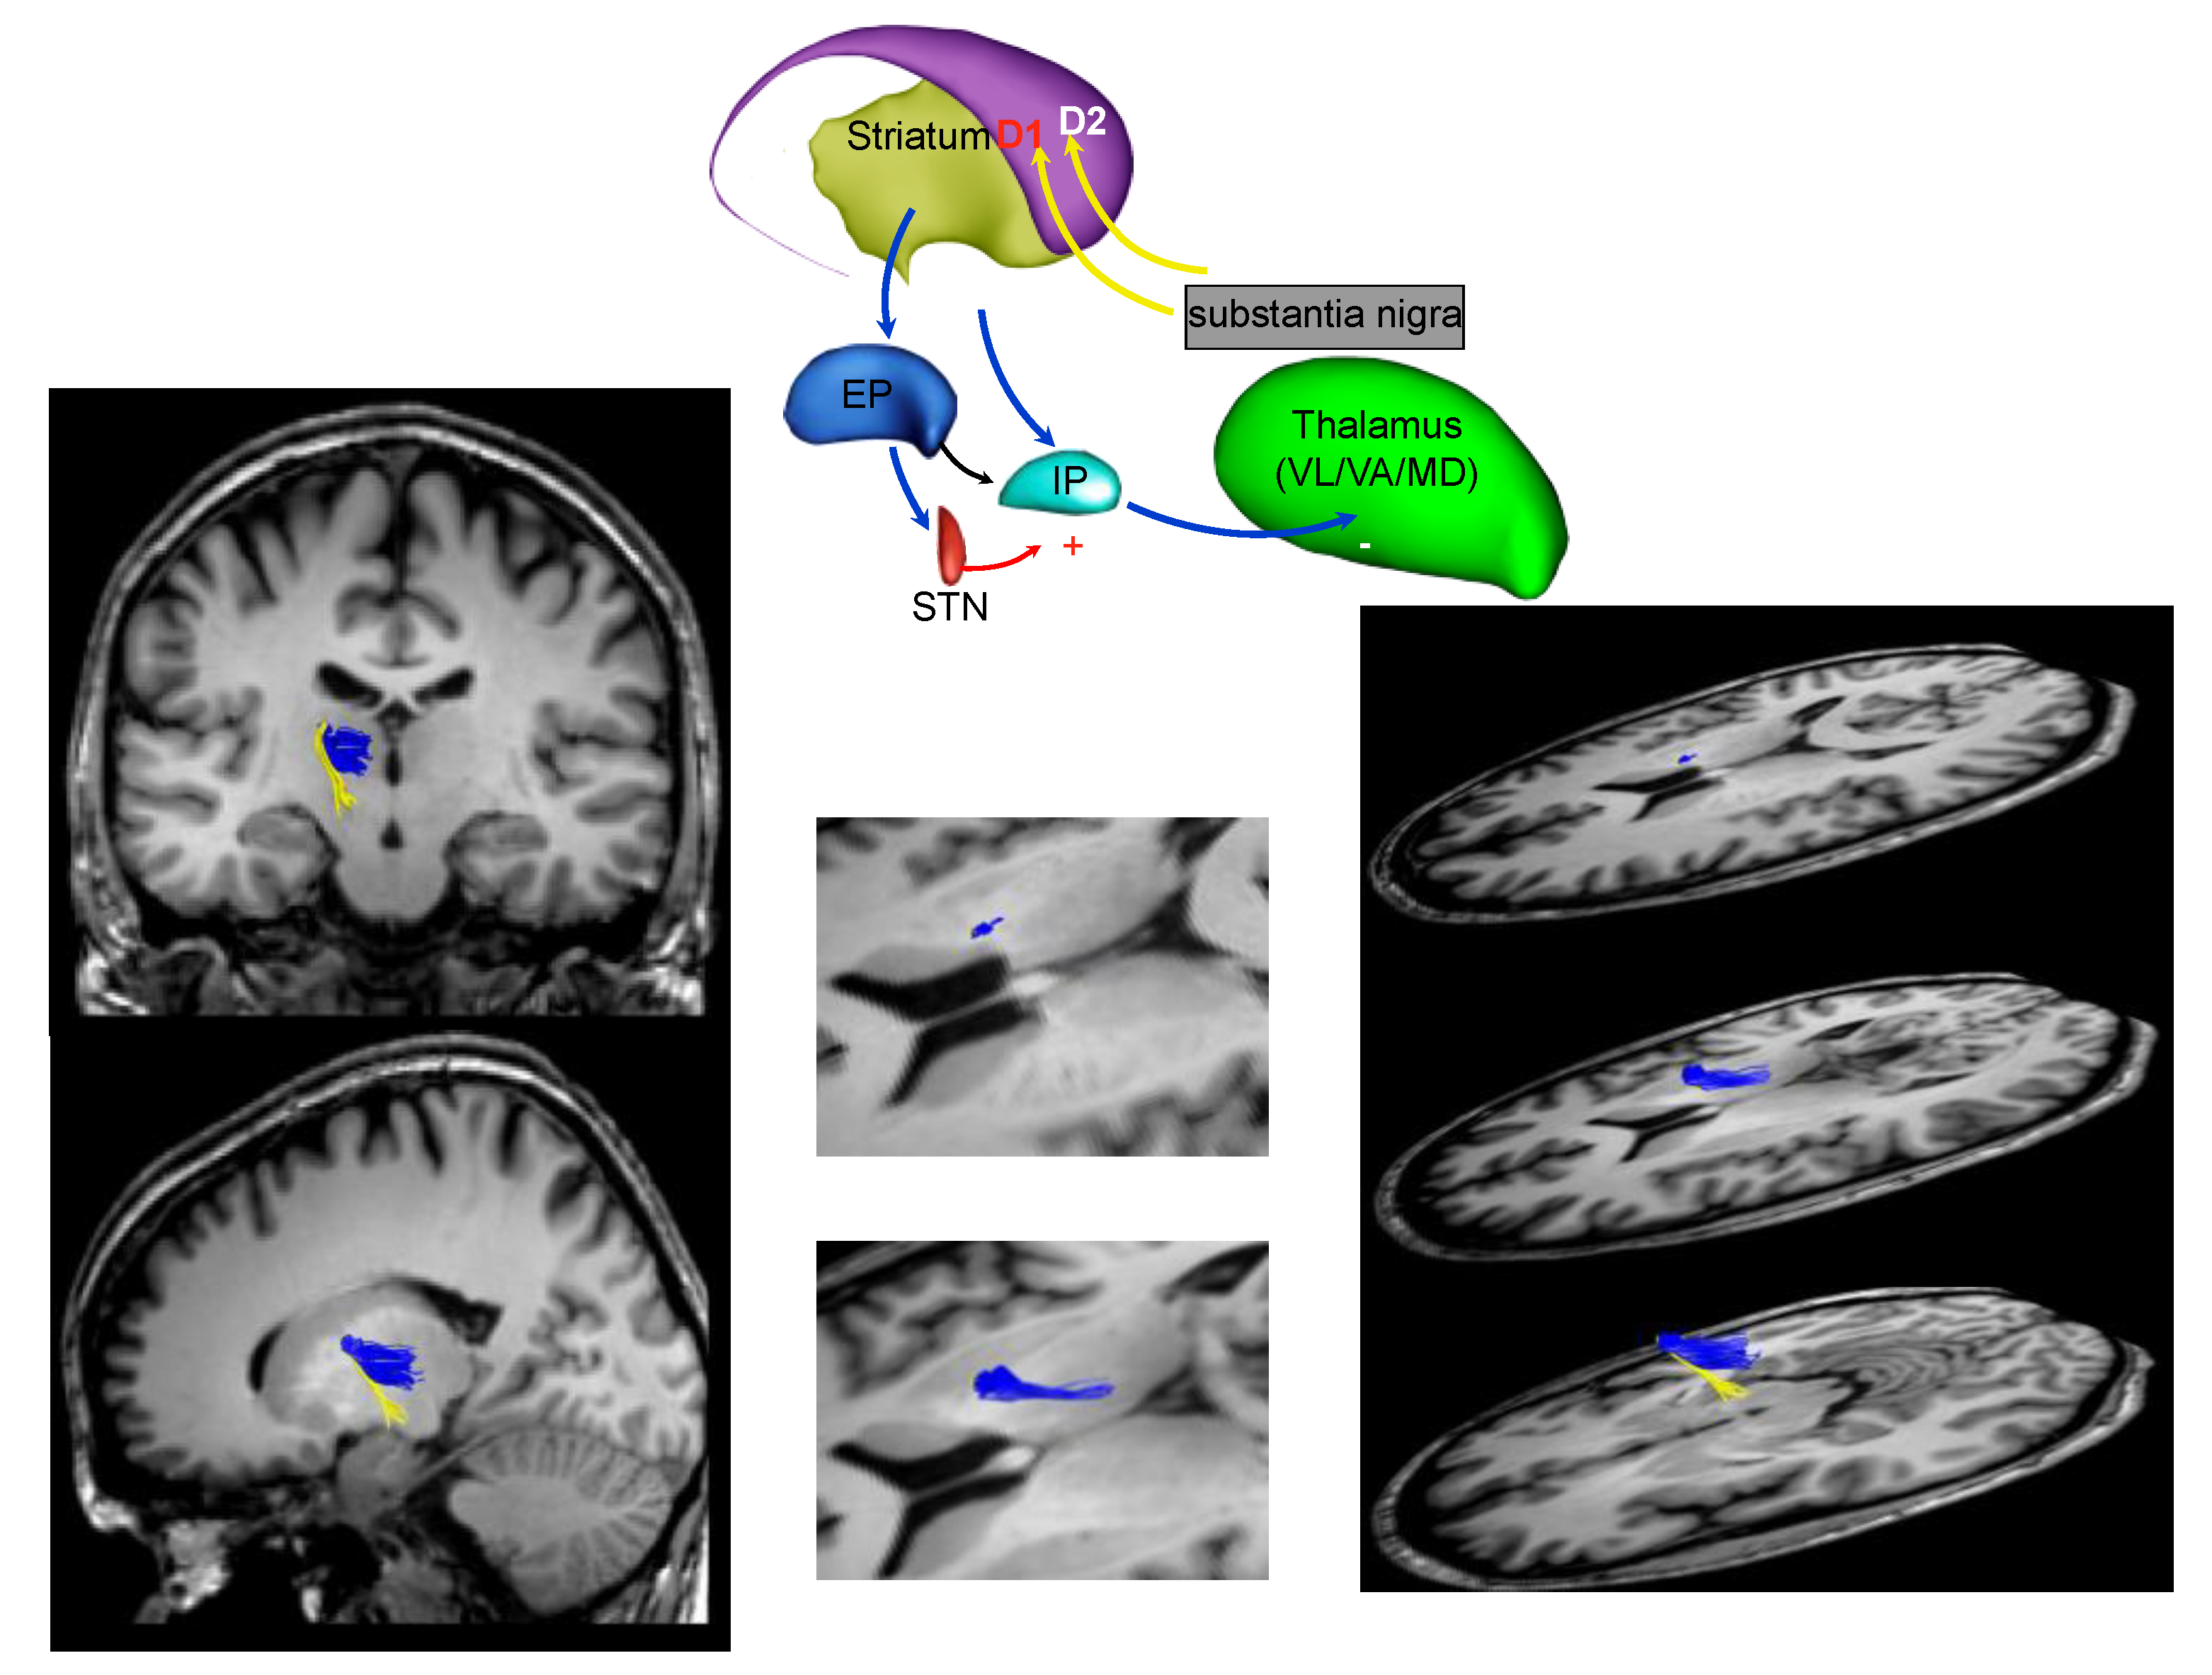

2.1. Structural Magnetic Resonance Imaging (sMRI)

3. Parkinson’s Disease Subtypes Identified by Tractography